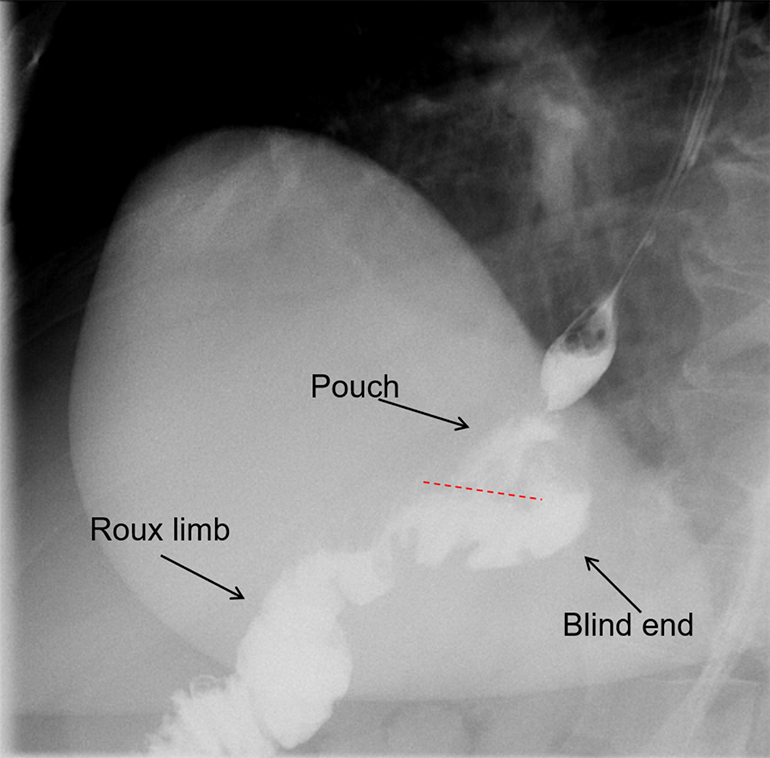

- Obtain a spot film of the contrast material filling the gastric pouch and proximal roux limb

(key image 2).

- Repeat steps b and c except have the patient positioned in the left posterior oblique position

(key image 3).

- If the contrast material has not progressed beyond the jejunojejunal anastomosis on the first radiograph, have the technologist obtain a delayed radiograph (more than one may be needed). Once the contrast has progressed past the jejunojejunal anastomosis, the procedure is complete

(key image 5)

(key image 6)

(key image 7).